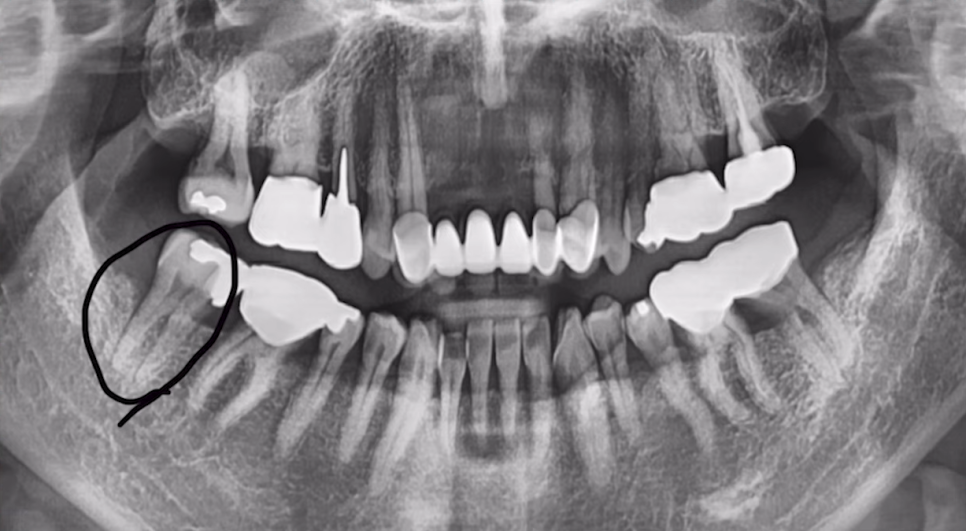

하나 사례를 들고 와봤는데요.

48세 여성 환자분이셨는데, '오른쪽 아래 치아가 아파요'라며 찾아주신 분입니다.

살펴보니 우측 제1대구치가 금이 가서 더 이상 유지가 어려운 상태였지요.

결국, 환자분의 동의를 받고 발치하였는데요.

감염도 거의 없고, 엑스레이 상 치조골도 잘 보존되어 있었기에 그날 바로 심어드렸습니다.

임플란트도 좋은 각도로 심고, 힐링 어버트먼트까지 잘 심어드렸습니다.

이렇게 발치 후 즉시 임플란트가 가능하려면 발치한 자리에 남은 뼈가 온전해야 합니다.

이를 뽑고 나면, 그 자리에 잇몸뼈가 남는데

이 뼈가 무너지지 않고 건강하게 남아 있어야 임플란트를 단단히 고정할 수 있거든요.